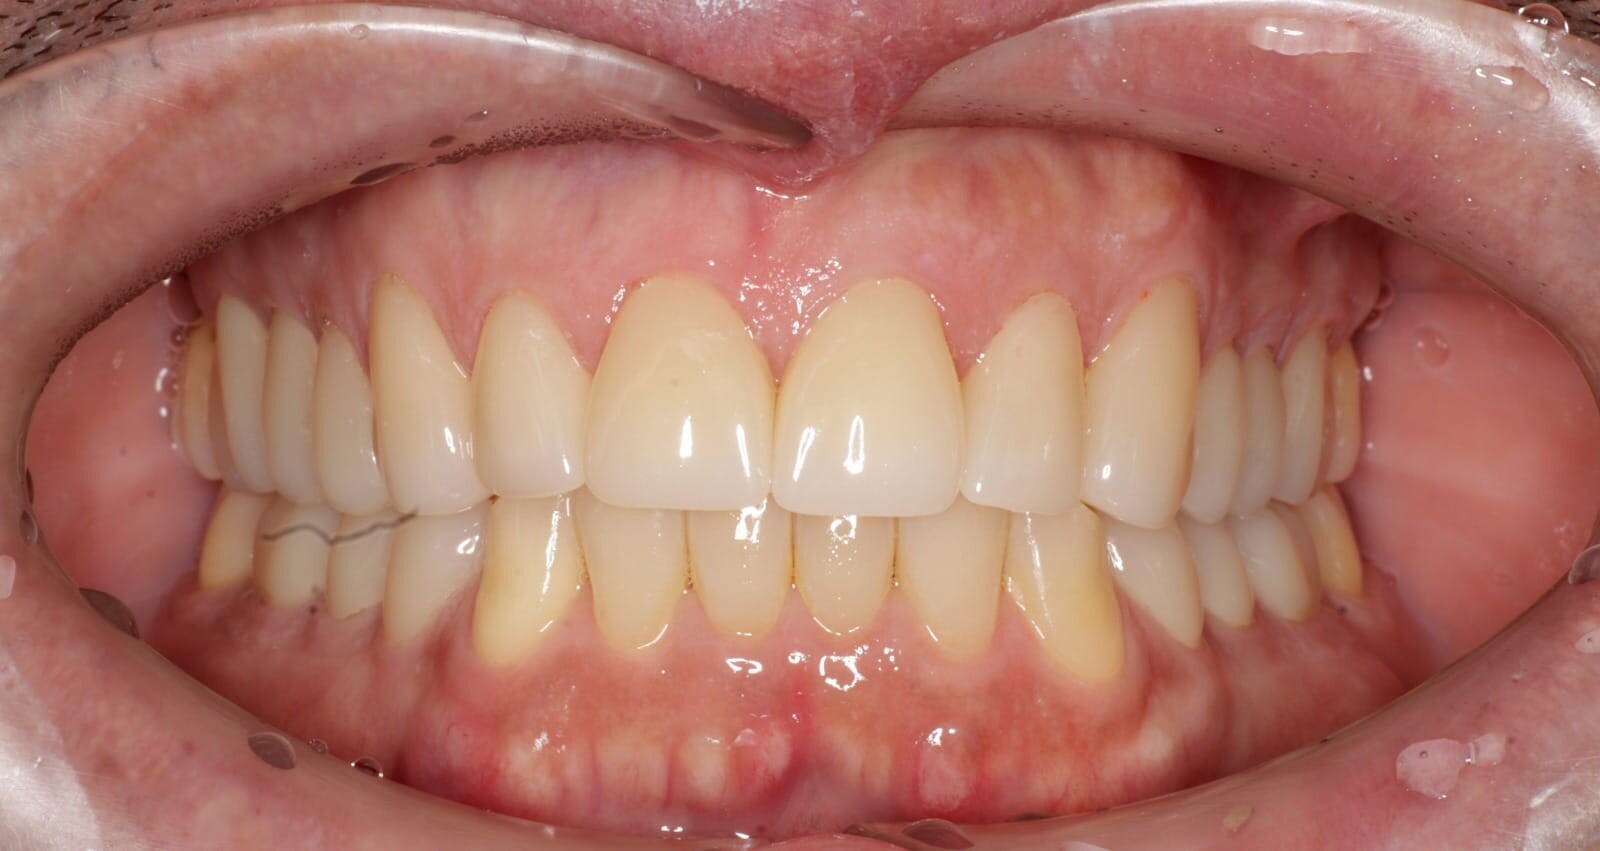

Fotografía digital intraoral de una reconstrucción de zirconia.

Fotografía intraoral a boca cerrada de una reconstrucción de zirconia de todas las piezas posteriores y de las áreas posteriores inferiores.